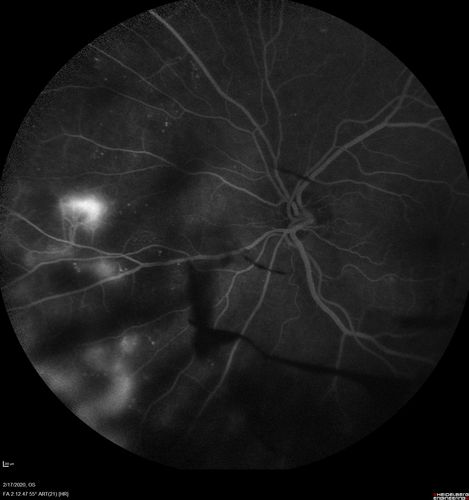

PDR and Vitreous Hemorrhage - High Risk Left Eye - Low Risk Right Eye

50 year old man with type I diabetes mellitus for 26 years. New Vitreous Hemorrhage in the left eye. Both eyes have NVE. Both also have foveal hypoplasia

Vitreous Hemorrhage and Proliferative Diabetic Retinopathy - Low risk right eye - High Risk Left Eye - Also Fovea Plana